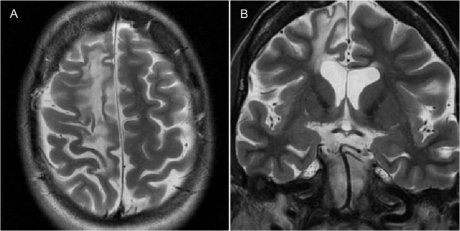

Hình 1.14. Tổn thương não do huyết khối tĩnh mạch não

(Hình ảnh do người viết cung cấp)